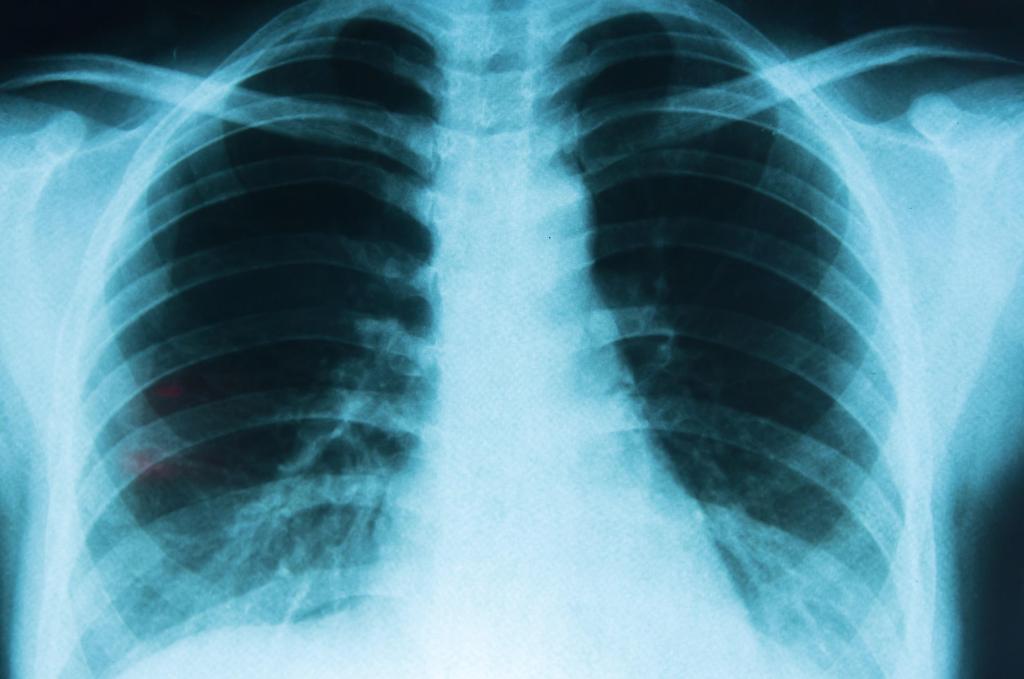

Especialistas dieron a conocer que uno de los principales problemas del cáncer de pulmón es que se detecta tarde.

Expertos sugieren que si eres una persona fumadora o fumaste durante un periodo de tu vida, realices una tomografía de baja dosis de forma anual para detectar anomalías oportunamente.